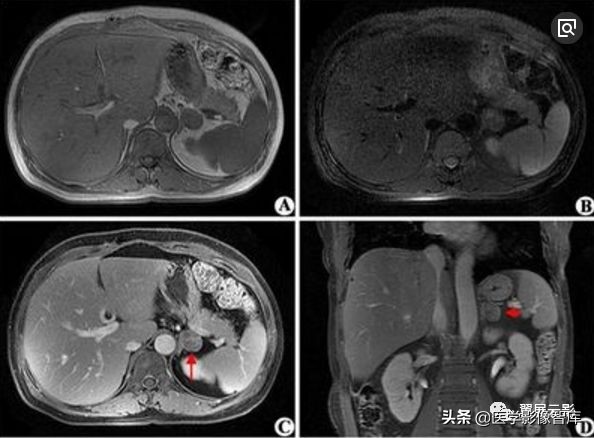

肾上腺转移瘤

肾上腺由于血供丰富,转移瘤很常见,在血行性转移的好发部位中占第四位,肾上腺转移瘤常见的原发性肿瘤是肺癌,乳腺癌,其次是胃癌,肝癌,胰腺癌,甲状腺癌,肾癌以及黑色素瘤与淋巴瘤,肾上腺转移瘤通常很少影响肾上腺功能,因而不见其本身内分泌症状;仅有很少肾上腺转移瘤产生肾上腺素分泌减少的表现。

右侧肾上腺小腺瘤

应该注意描述肾上腺转移瘤的特点,肿瘤一般为双侧性,边缘较不规则,由于肿瘤出血坏死,信号较不均匀,T2WI信号较高,动态增强扫描转移瘤一般强化明显且持续较长时间,注意询问病史,确定原发灶。邻近其他脏器的转移性病灶和腹膜后肿大淋巴结也应观察描述。